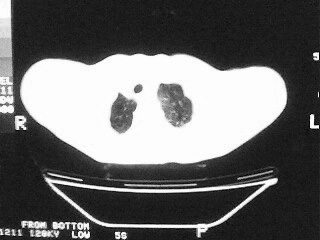

女,79,咳 嗽月余,无其它不适

后纵隔内左心房至肝左叶后方椎体中线偏左巨大软组织包块,其壁均匀比较薄,其内可见宽气液平。

考虑食管裂孔疝。建议钡餐检查